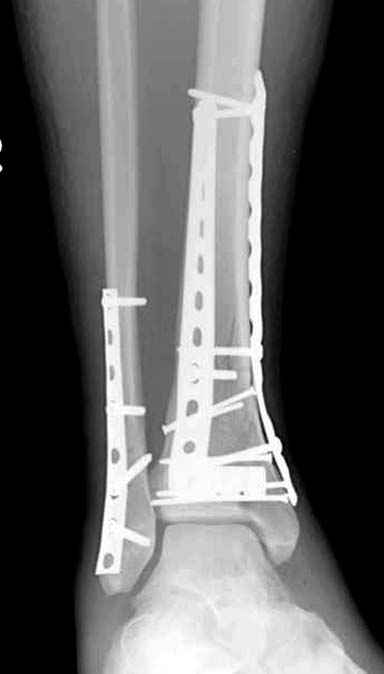

Спасибо за советы. Выполнен МОС обоих костей голени

Lig. tibiofibulare anterius оказалась целой. Был выявлен разрыв межкостной мембраны между берцовыми костями.

Разрыв межкостной мембраны между берцовыми костями был выявлен в зоне оперативного вмешвтельства на малоберцовой кости выше ее перелома. Логично было бы предположить, что он (разрыв) продолжается до проксимального синдесмоза голени. Но передняя межберцовая связка оказалась целой, поэтому ДМС оказался стабилен.

По представленным послеоперационным снимкам создаётся впечатление сохраняющегося подвывиха + итраоперационно обнаруженный разрыв межкостной мембраны.

Извините за некачественные снимки и неправильную укладку в прямой проэкции. Подвывих рентгенологически не определяется. Кроме этого, после МОС малоберцовой кости интраоперационно однозубым крючком проверена стабильность синдесмоза - он стабилен. Кроме этого, интраоперационно проверена стабильность стопы в голеностопе - люфта ее при боковых отклонениях не определяется, также визуально при этом приеме отклонения малоберцовой кости кнаружи в ДМС не определяется. В дополнение к этому (у ассистента были сомнения) был сделан доступ к межберцовой связке и ее визуальный осмотр- она оказалась целой. При данных обстоятельствах позиционный винт мы не вводим.

В обсуждаемом случае есть полный разрыв одной из важных составляющих дистального межберцового синдесмоза - межкостной мембраны. Зачастую при полном разрыве lig.tibiofibulare anterius после остеосинтеза лодыжки пластиной межкостная мембрана настолько прочно удерживает вилку сустава, что кроме шва дистального межберцового синдесмоза, введение позиционного винта не обязательно. Но в представленном случае разрыв межкостной мемраны особого значения не имеет, т.к. lig.tibiofibulare anterius цела. Поэтому ДМС поврежден частично, хотя практического значения это не имеет. Остеосинтез малоберцовой выполнен в большей мере потому, что пациент хотел обойтись без внешней иммобилизации.

Теперь о другом. Бережное отношение к тканям - это довольно философский вопрос. Есть мнения, что хорошей репозицией можно пренебречь, а главное - в меньшей мере травмировать надкостницу. Идеальная репозиция простого винтообразного перелома (студенческого) большеберцовой кости с скосом в 2,5 - 3 диаметра и МОС по правилам АО в сочетании с бережным (или не очень) отношением к надкостнице при отсутствии воспаления всегда (по моему опыту) приводит к консолидации в обычные сроки. До, можно было синтезировать и 3 - 5 винтами с чуть меньшего разреза (проксимальные 4 см пластины проведены под кожей), но все же это менее стабильно, чем МОС пластиной. Мне очень интересно понять Ваше мнение, какие детали послеоперационных рентгенограмм косвенно свидетельствуют об отношении хирурга к мягким тканям.

Данная фиксация пластинами сделана классическим АО методом описанным еще в 1989 году в книге J. Mast и R. Ganz “Planning and Reduction Technique in Fracture Surgery”. В то время antiglade method DCP пластиной в 4.5 мм c повторением натурального изгиба голени в н/3 считался одним из оригинальных. Повторение оригинальной концепции и фиксация спонгиозными шурупами в дистальном отделе доказывает, что коллеги хорошо освоили метод АО. Но для уменьшения раздражения пластиной изнутри в нижнем отделе, авторы применяли технику погружения пластины в кортекс. Профилактические меры не всегда помогали, и в неумелых руках "передне-медиальный АО доступ" часто осложнялся кожными осложнениями.

Без современных материалов создать хорошую фиксацию становится трудной задачей, и этот случай характерен тем, что достигнутую идеальную репозицию испортили старомодной техникой. Исследования показали, что спонгиозные шурупы в метафизарных частях не создают механические преимущества как считали раньше. Кортикальные винты менее агрессивны и не оставляют дефекта кости после их удаления.

Низкопрофильные преконтурированные пластины с угловой стабильностью создают меньше проблем с медиальным покрытием, а толстая пластина становится раздражителем после спадения отека.